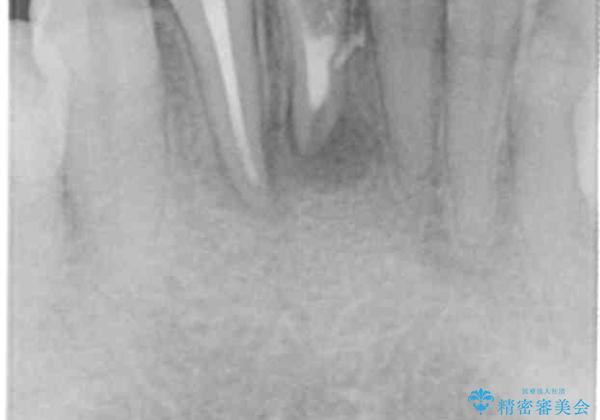

X線写真検査より根尖性歯周炎が認められたため、根管再治療を行いemaxクラウンを装着する治療計画を立てます。

再根管治療を行ったことで、感染が除去され根尖の病変が小さくなってきていることがX線写真検査よりわかります。